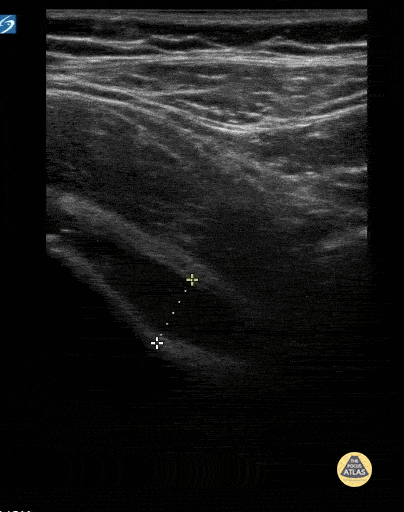

Peds-MSK - Hip Effusion in 6yo 2/2 Transient Synovitis

6 yo with acute onset limp. Afebrile. Decreased ROM of the left hip. POCUS showed a hip effusion consistent with the diagnosis of transient synovitis. Contributor: Kathryn Pade, MD, Rady Children's Hospital San Diego